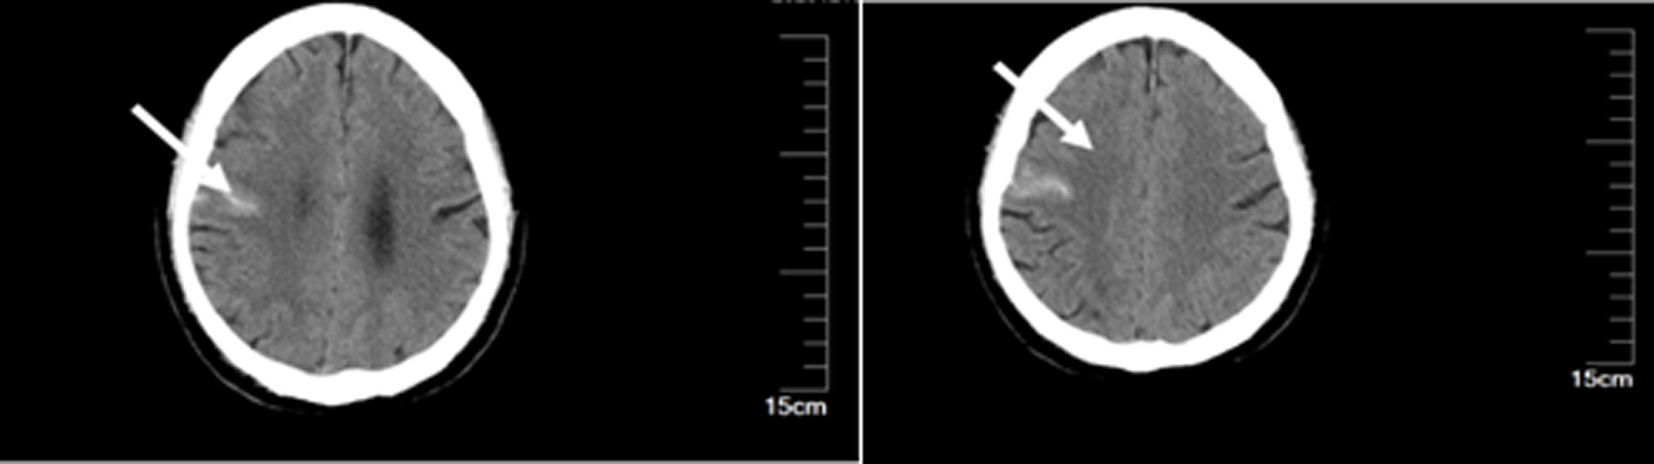

Charidimou A, Boulouis G, Fotiadis P, et al. Acute convexity subarachnoid haemorrhage and cortical superficial siderosis in probable cerebral amyloid angiopathy without lobar haemorrhage[J]. J Neurol Neurosurg Psychiatry, 2018, 89(4):397-403. doi: 10.1136/jnnp-2017-316368.

Ly JV, Ma H, Shaloo S, et al. Convexity subarachnoid haemorrhage: A practical guide[J]. Pract Neurol, 2023, 23(5):368-375. doi: 10.1136/pn-2022-003572.

徐秀红, 李波, 徐玉, 等. 脑凸面蛛网膜下腔出血合并脑梗死两例报道并文献复习[J]. 实用心脑肺血管病杂志, 2023, 31(1):130-135.

Zhao H, Han J, Lu M, et al. Incidence and possible causes of nontraumatic convexal subarachnoid haemorrhage in Chinese patients: A retrospective review[J]. J Int Med Res, 2017, 45(6):1870-1878. doi: 10.1177/0300060516651987.

Zedde M, Grisendi I, Assenza F, et al. Spontaneous non-aneurysmal convexity subarachnoid hemorrhage: A scoping review of different etiologies beyond cerebral amyloid angiopathy[J]. J Clin Med, 2024, 13(15):4382. doi: 10.3390/jcm13154382.

杜万良, 荆京, 王伊龙, 等. 自发性凸面蛛网膜下腔出血的临床和影像学特点[J]. 中国卒中杂志, 2015, 10(7):580-585.